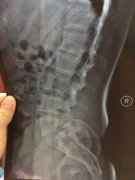

• “闪腰”不加重视 以致患上强直

该患者的相关情况,由蒙兴文主任的助理医生跟踪记录,内容属实 ...